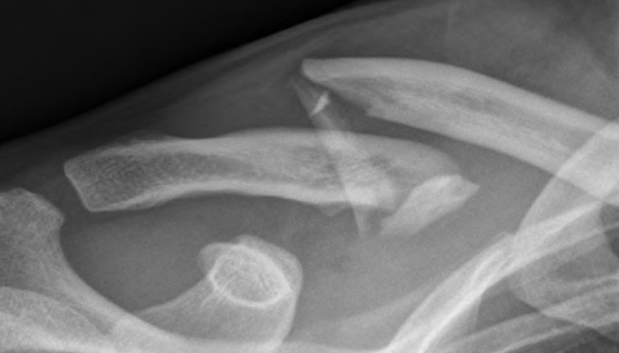

İşte kırıklar hakkında doğru bildiğimiz 5 yanlış! - Resim: 3

YAŞLI İNSANLARIN VÜCUDU KIRIĞA DAHA MI YATKIN? İleri yaştaki kadınlarda kemikte kırılma riskinin gençlere göre daha fazla olduğu doğrudur. Menopoz nedeniyle hormonlarda yaşanan değişim kemik yoğunluğunda ani düşüşe yol açtığı için, kemik erimesi (osteoporoz) kaynaklı kırıklara sık rastlanır. ABD'de beyaz kadınlarda kalça kırılması siyah kadınların iki katı düzeyindedir.